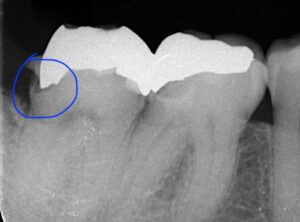

レントゲンの青丸の部分が被せ物の下の虫歯になります。

歯茎の中になりますので器具が入りません。